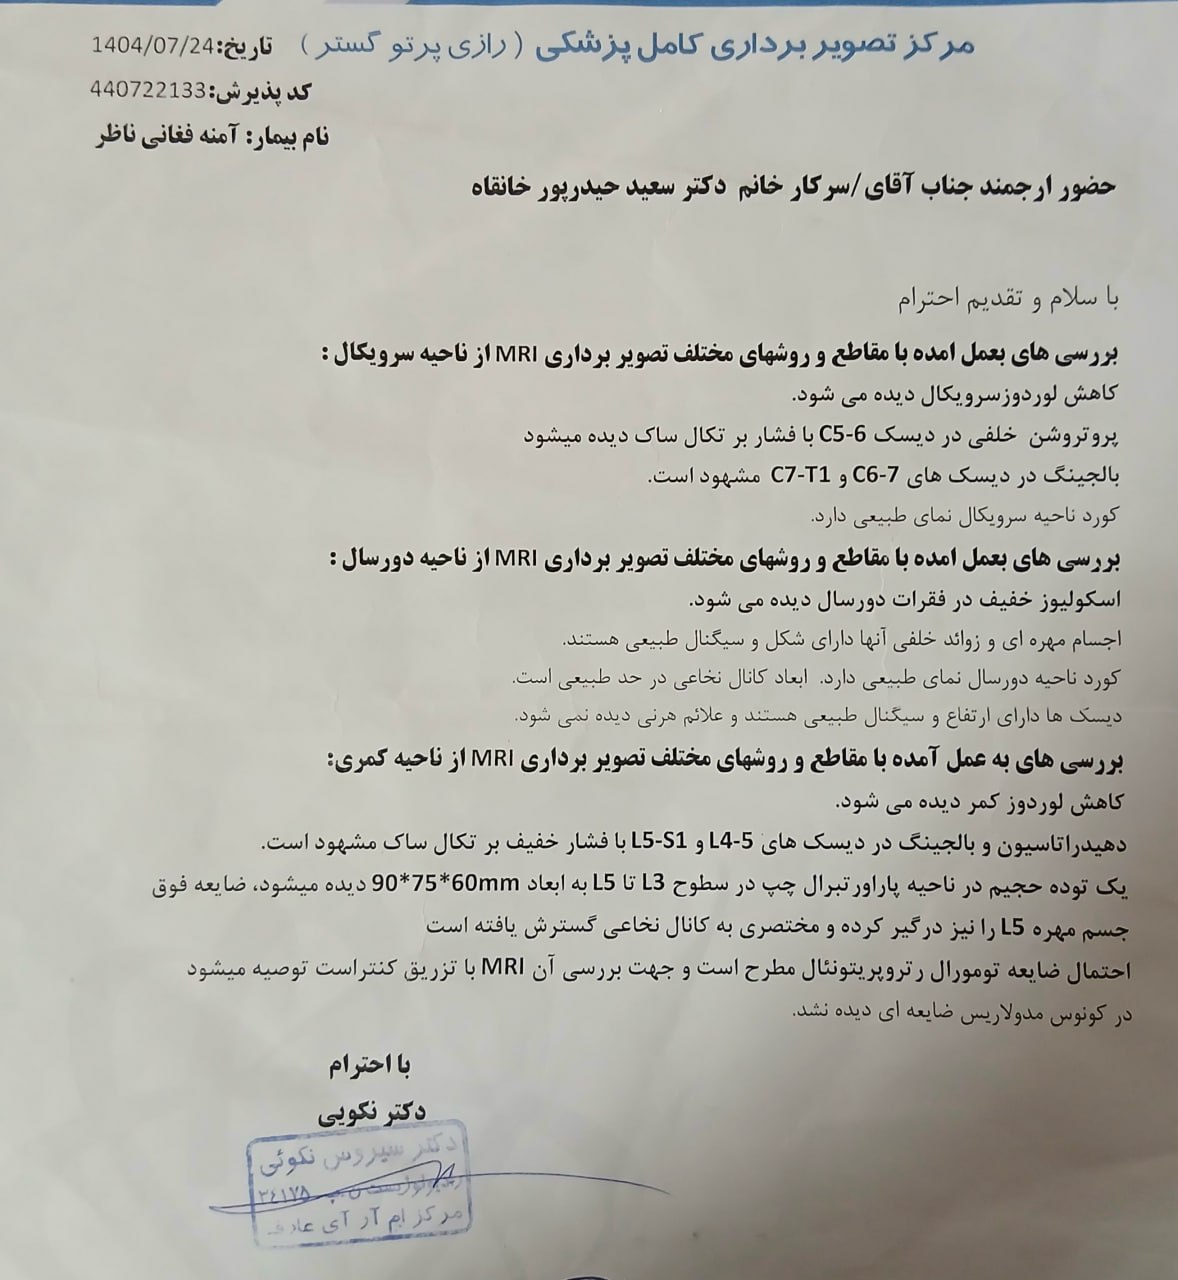

در بررسیهای تصویربرداری (MRI)،در تاریخ 24.7 ، تودهای با تشخیص کندروسارکوما همراه با DVT گزارش شده است. بیمار سابقه درد لگن داشته که شدت آن در حال حاضر نسبت به گذشته کاهش یافته است. به گفته بیمار، حجم توده در ابتدا در حدود اندازه یک تخممرغ بوده که در حال حاضر کاهش یافته است. همچنین تورم اندام تحتانی در حال حاضر نسبت به قبل کمتر شده است.

(تصویر مربوط به این مراجعه نیست) Other:

(تصویر مربوط به این مراجعه نیست) Other: